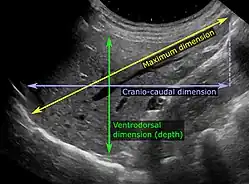

Ultrasonography of the liver with some standard measurements[6]

Ultrasonography of liver tumors involves two stages: detection and characterization. Tumor detection is based on the performance of the method and should include morphometric information (three axes dimensions, volume) and topographic information (number, location specifying liver segment and lobe/lobes). The specification of these data is important for staging liver tumors and prognosis. Tumor characterization is a complex process based on a sum of criteria leading towards tumor nature definition. Often, other diagnostic procedures, especially interventional ones, are no longer necessary. Tumor characterization using the ultrasound method will be based on the following elements: consistency (solid, liquid, mixed), echogenicity, structure appearance (homogeneous or heterogeneous), delineation from adjacent liver parenchyma (capsular, imprecise), elasticity, posterior acoustic enhancement effect, the relation with neighboring organs or structures (displacement, invasion), vasculature (presence and characteristics on Doppler ultrasonography and contrast-enhanced ultrasound (CEUS).